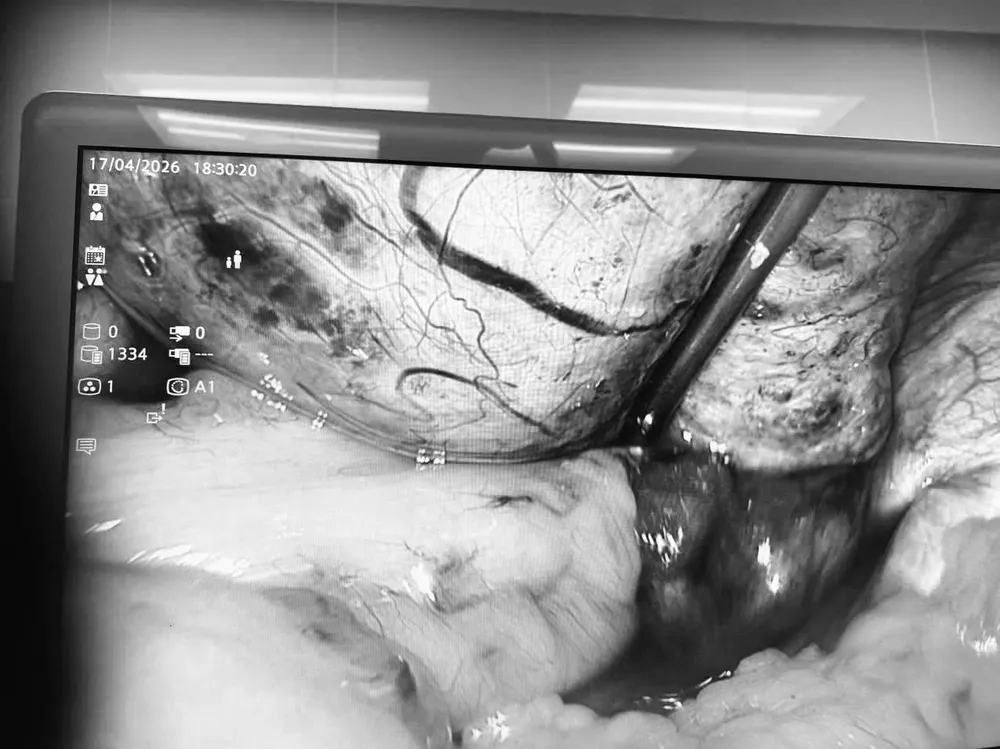

Trong quá trình nội soi, các bác sĩ ghi nhận khối u nang lớn cạnh buồng trứng phải, kéo theo tai vòi và buồng trứng xoắn đến 5 vòng, chuyển màu tím đen do thiếu máu nuôi.

Ê-kíp phẫu thuật đã tiến hành tháo xoắn, cắt bỏ u nang dạng bì. Sau can thiệp, buồng trứng và tai vòi hồi phục màu hồng và được bảo tồn hoàn toàn nhờ xử trí kịp thời.

Quá trình nội soi cắt bỏ khối u